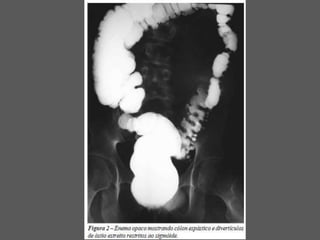

MEGA COLON – CONGENITO OU

ADQUIRIDA